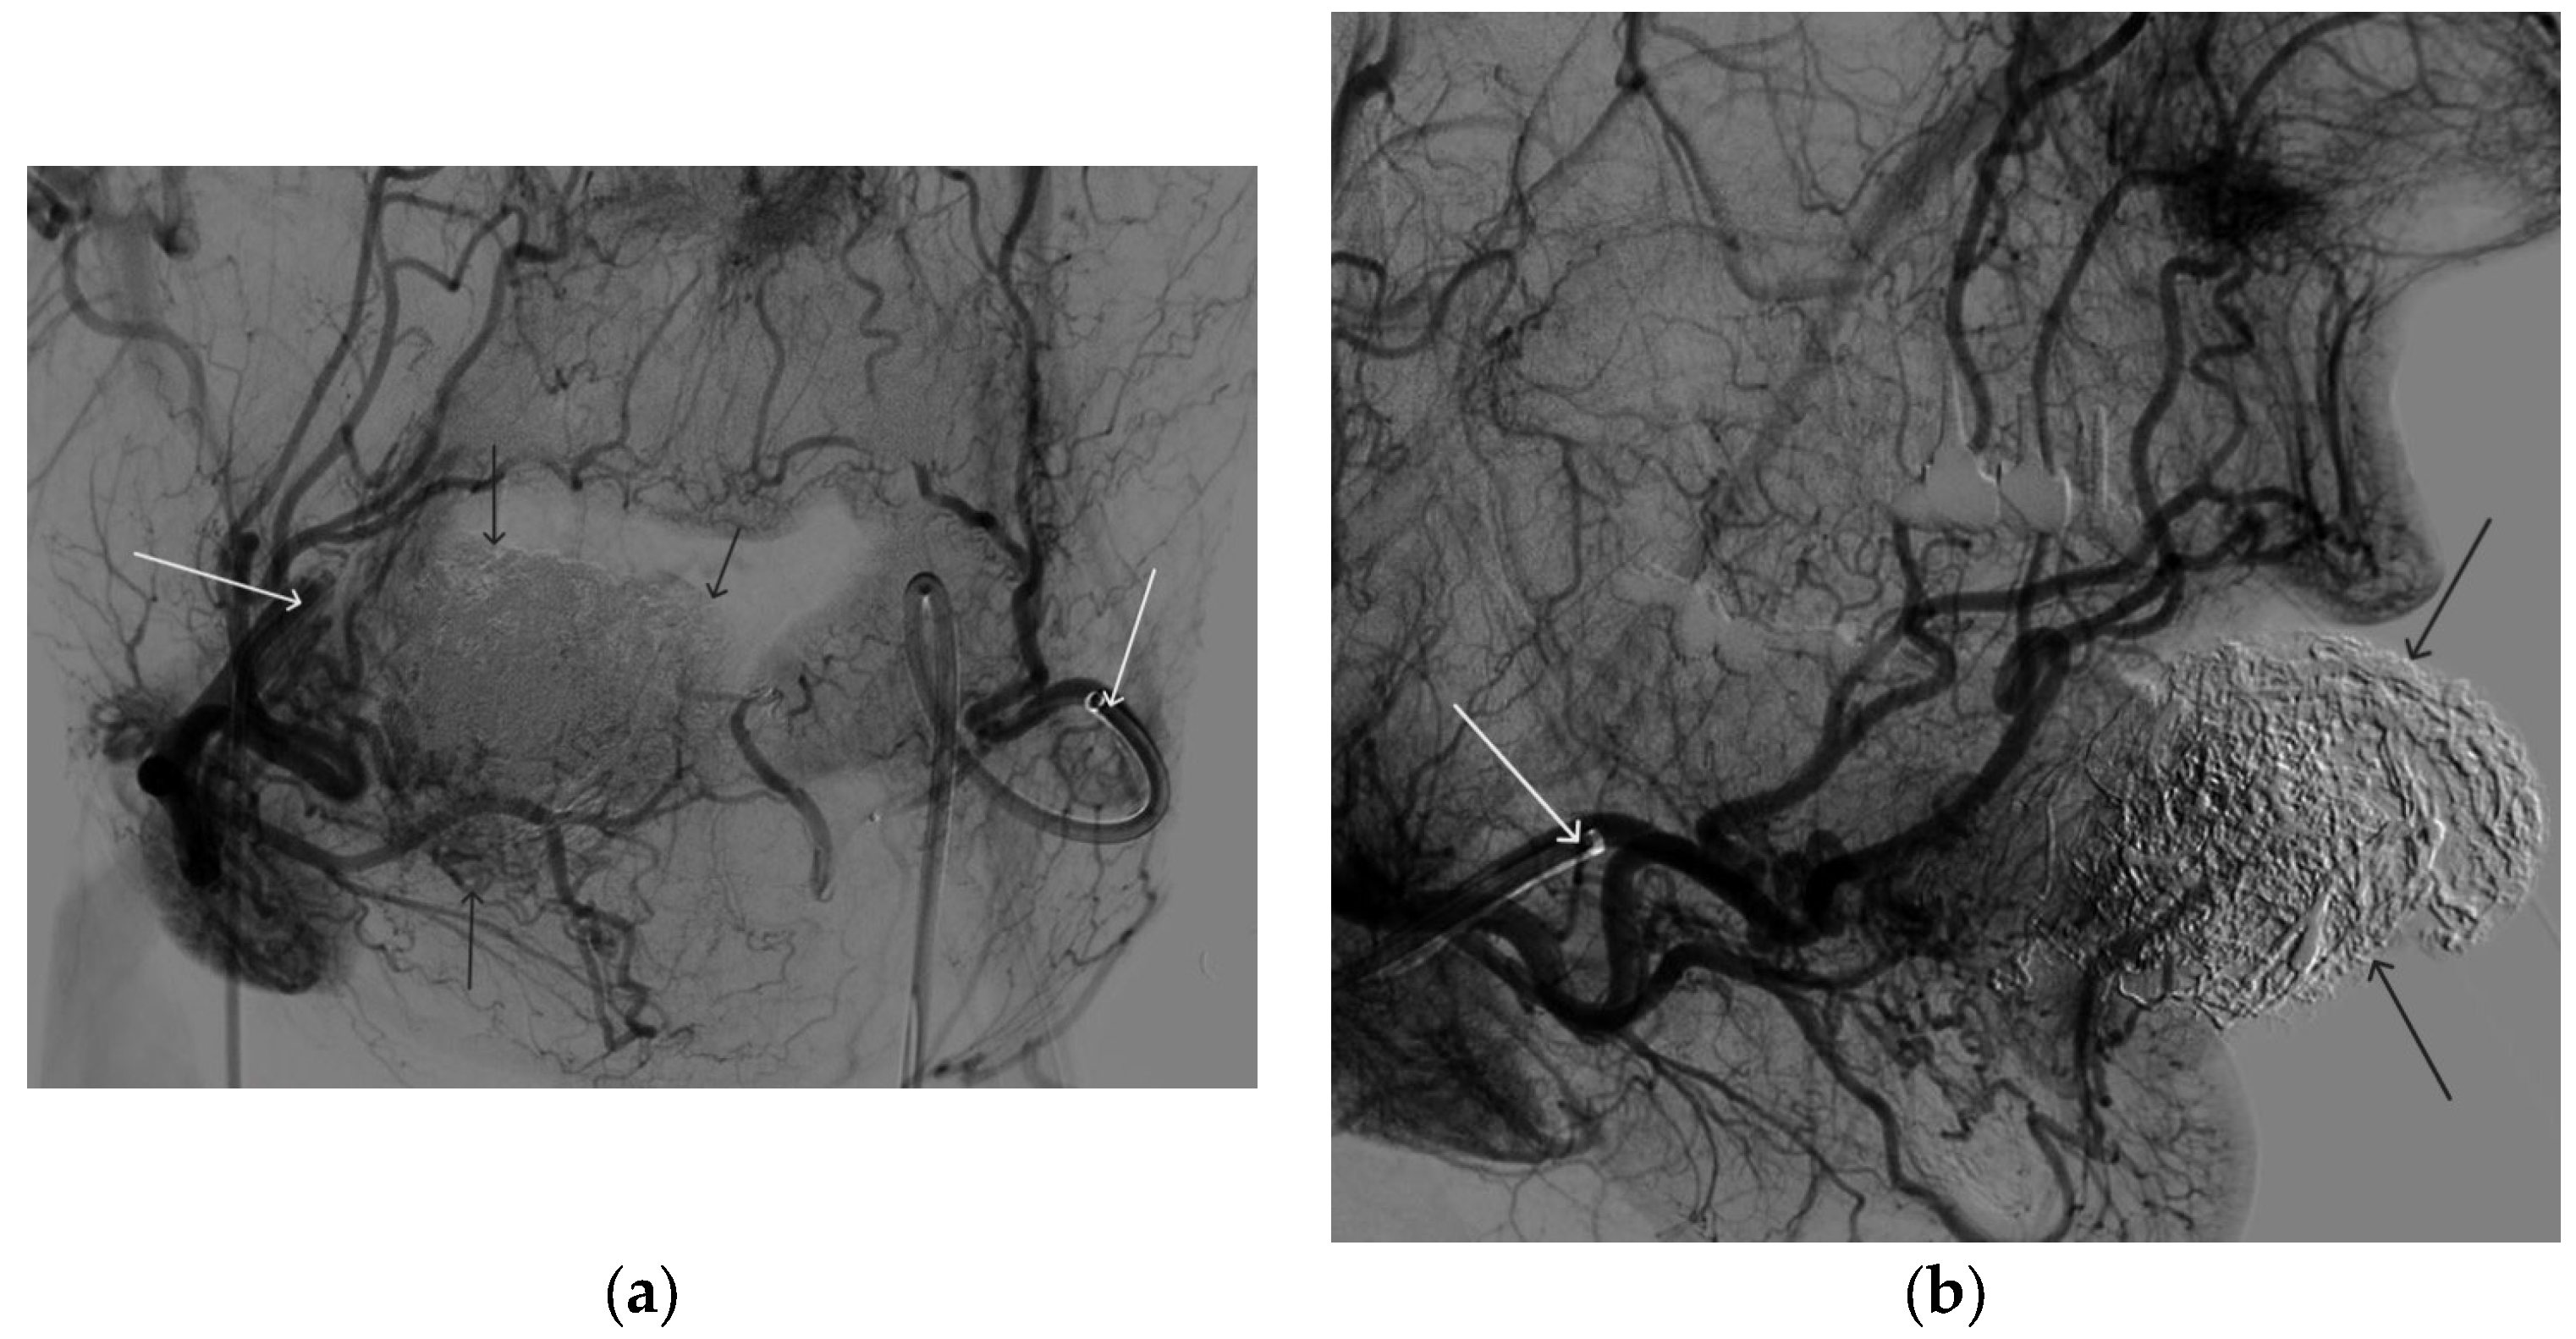

Figure 6. Digital subtraction angiography from the right and left facial arteries: (a) direct projection; (b) lateral projection (white arrows indicate catheters at the ostium of the facial arteries, black arrows indicate embolizate cast). The absence of AVM contrast is noted.